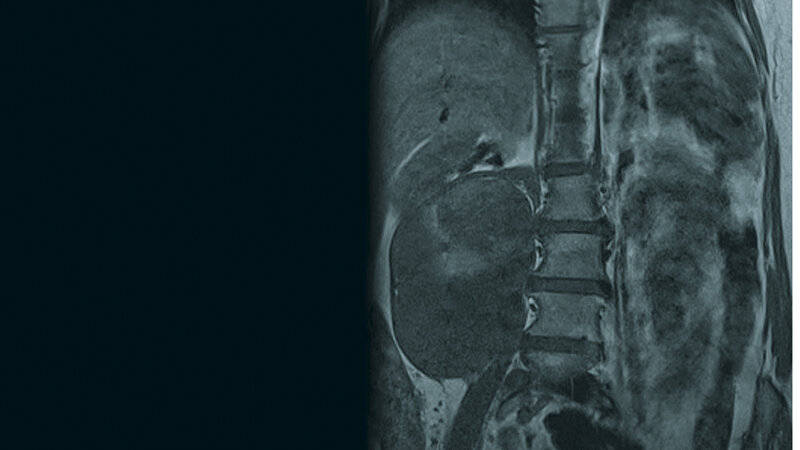

Zufallsbefunde: Retroperitoneales Liposarkom

Das Liposarkom ist das häufigste Weichteilsarkom und macht etwa 20 % der Sarkome des Erwachsenen aus. Retroperitoneale Weichteilsarkome haben wegen ihrer speziellen Lage die Tendenz, über einen langen Zeitraum asymptomatisch zu sein und eine beachtliche Größe zu erreichen, bevor sie diagnostiziert werden. CT und MRT sind gute diagnostische Methoden. Die Chirurgie spielt die dominante Rolle in der Behandlung. Low-grade-Tumoren und makroskopisch tumorfreies OP-Gebiet sind signifikant mit einem reduzierten Rezidivrisiko und verbesserter Überlebenschance verbunden.